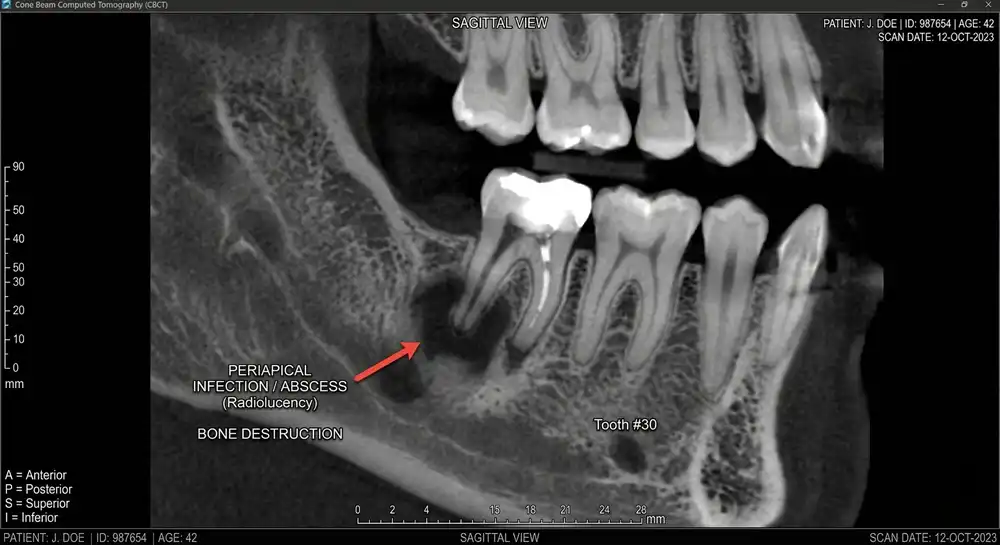

Can an Abscessed Tooth Become Life-Threatening?

A dental abscess forms when bacteria infect the pulp or surrounding bone. The infection produces pus and pressure inside the tissue.

Symptoms often include:

- severe throbbing pain

- gum swelling

- fever

- bad taste in the mouth

Technical detail: anaerobic bacteria

Many dental abscesses contain anaerobic bacteria, organisms that thrive in low-oxygen environments inside infected tissue. These bacteria can spread into surrounding tissues if untreated.

Rare complications include deep neck infections or systemic illness.

Prompt dental treatment removes the infection source and drains the abscess.

What Happens If I Wait Too Long to Treat a Dental Emergency?

Delaying treatment can lead to several complications:

- infection spreading to surrounding tissues

- permanent tooth loss

- bone damage around the tooth

Technical detail: bone resorption

When infection persists, inflammatory signals stimulate cells called osteoclasts, which break down bone tissue. This process, known as bone resorption, weakens support around the tooth.

Once significant bone loss occurs, saving the tooth becomes much harder.